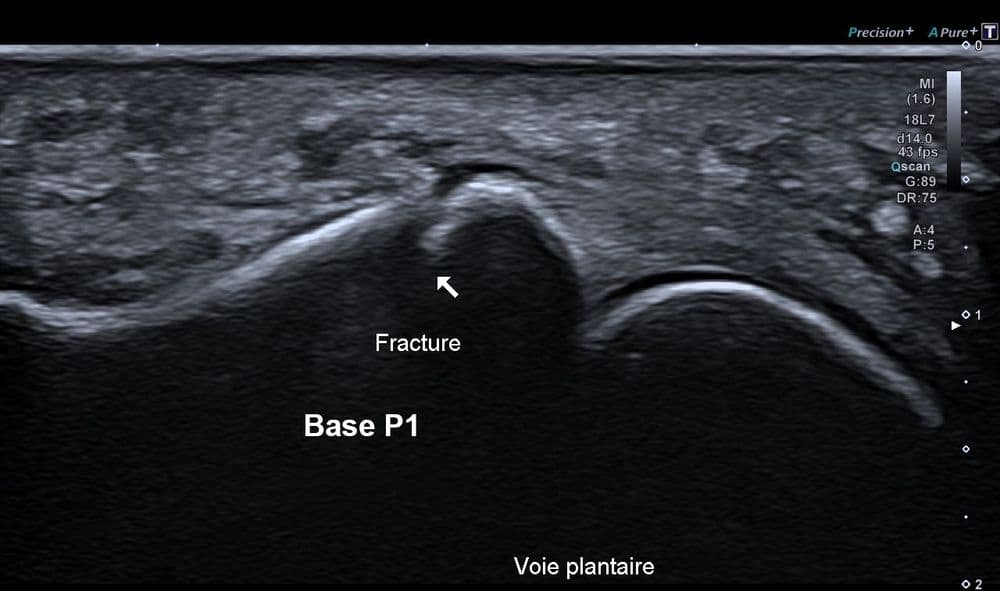

Fracture instable étudiée en échographie dynamique

US